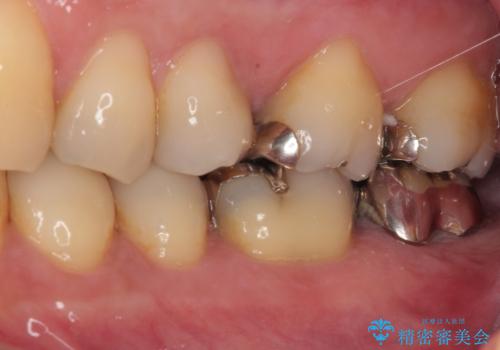

- 奥の銀歯が外れしまったとのことで来院された患者様です。

非常に咬合力が強く、銀歯の周りの歯がむし歯になっている状態でした。

部分的な詰め物ですと、再度周辺がむし歯になるリスクが高いと考えられたため、オールセラミッククラウンにて補綴治療を行うこととしました。

ゴールドのような金属の詰め物は、削る範囲を最小限にし、厚みもセラミックと比べて薄くできるため、セラミックのようにクラウンにせずに治療を行うこともできますが、保険診療である銀歯では、どうしても適合が悪く隙間ができてしまうので、今回のような周辺がむし歯になる可能性が高くなってしまいます。